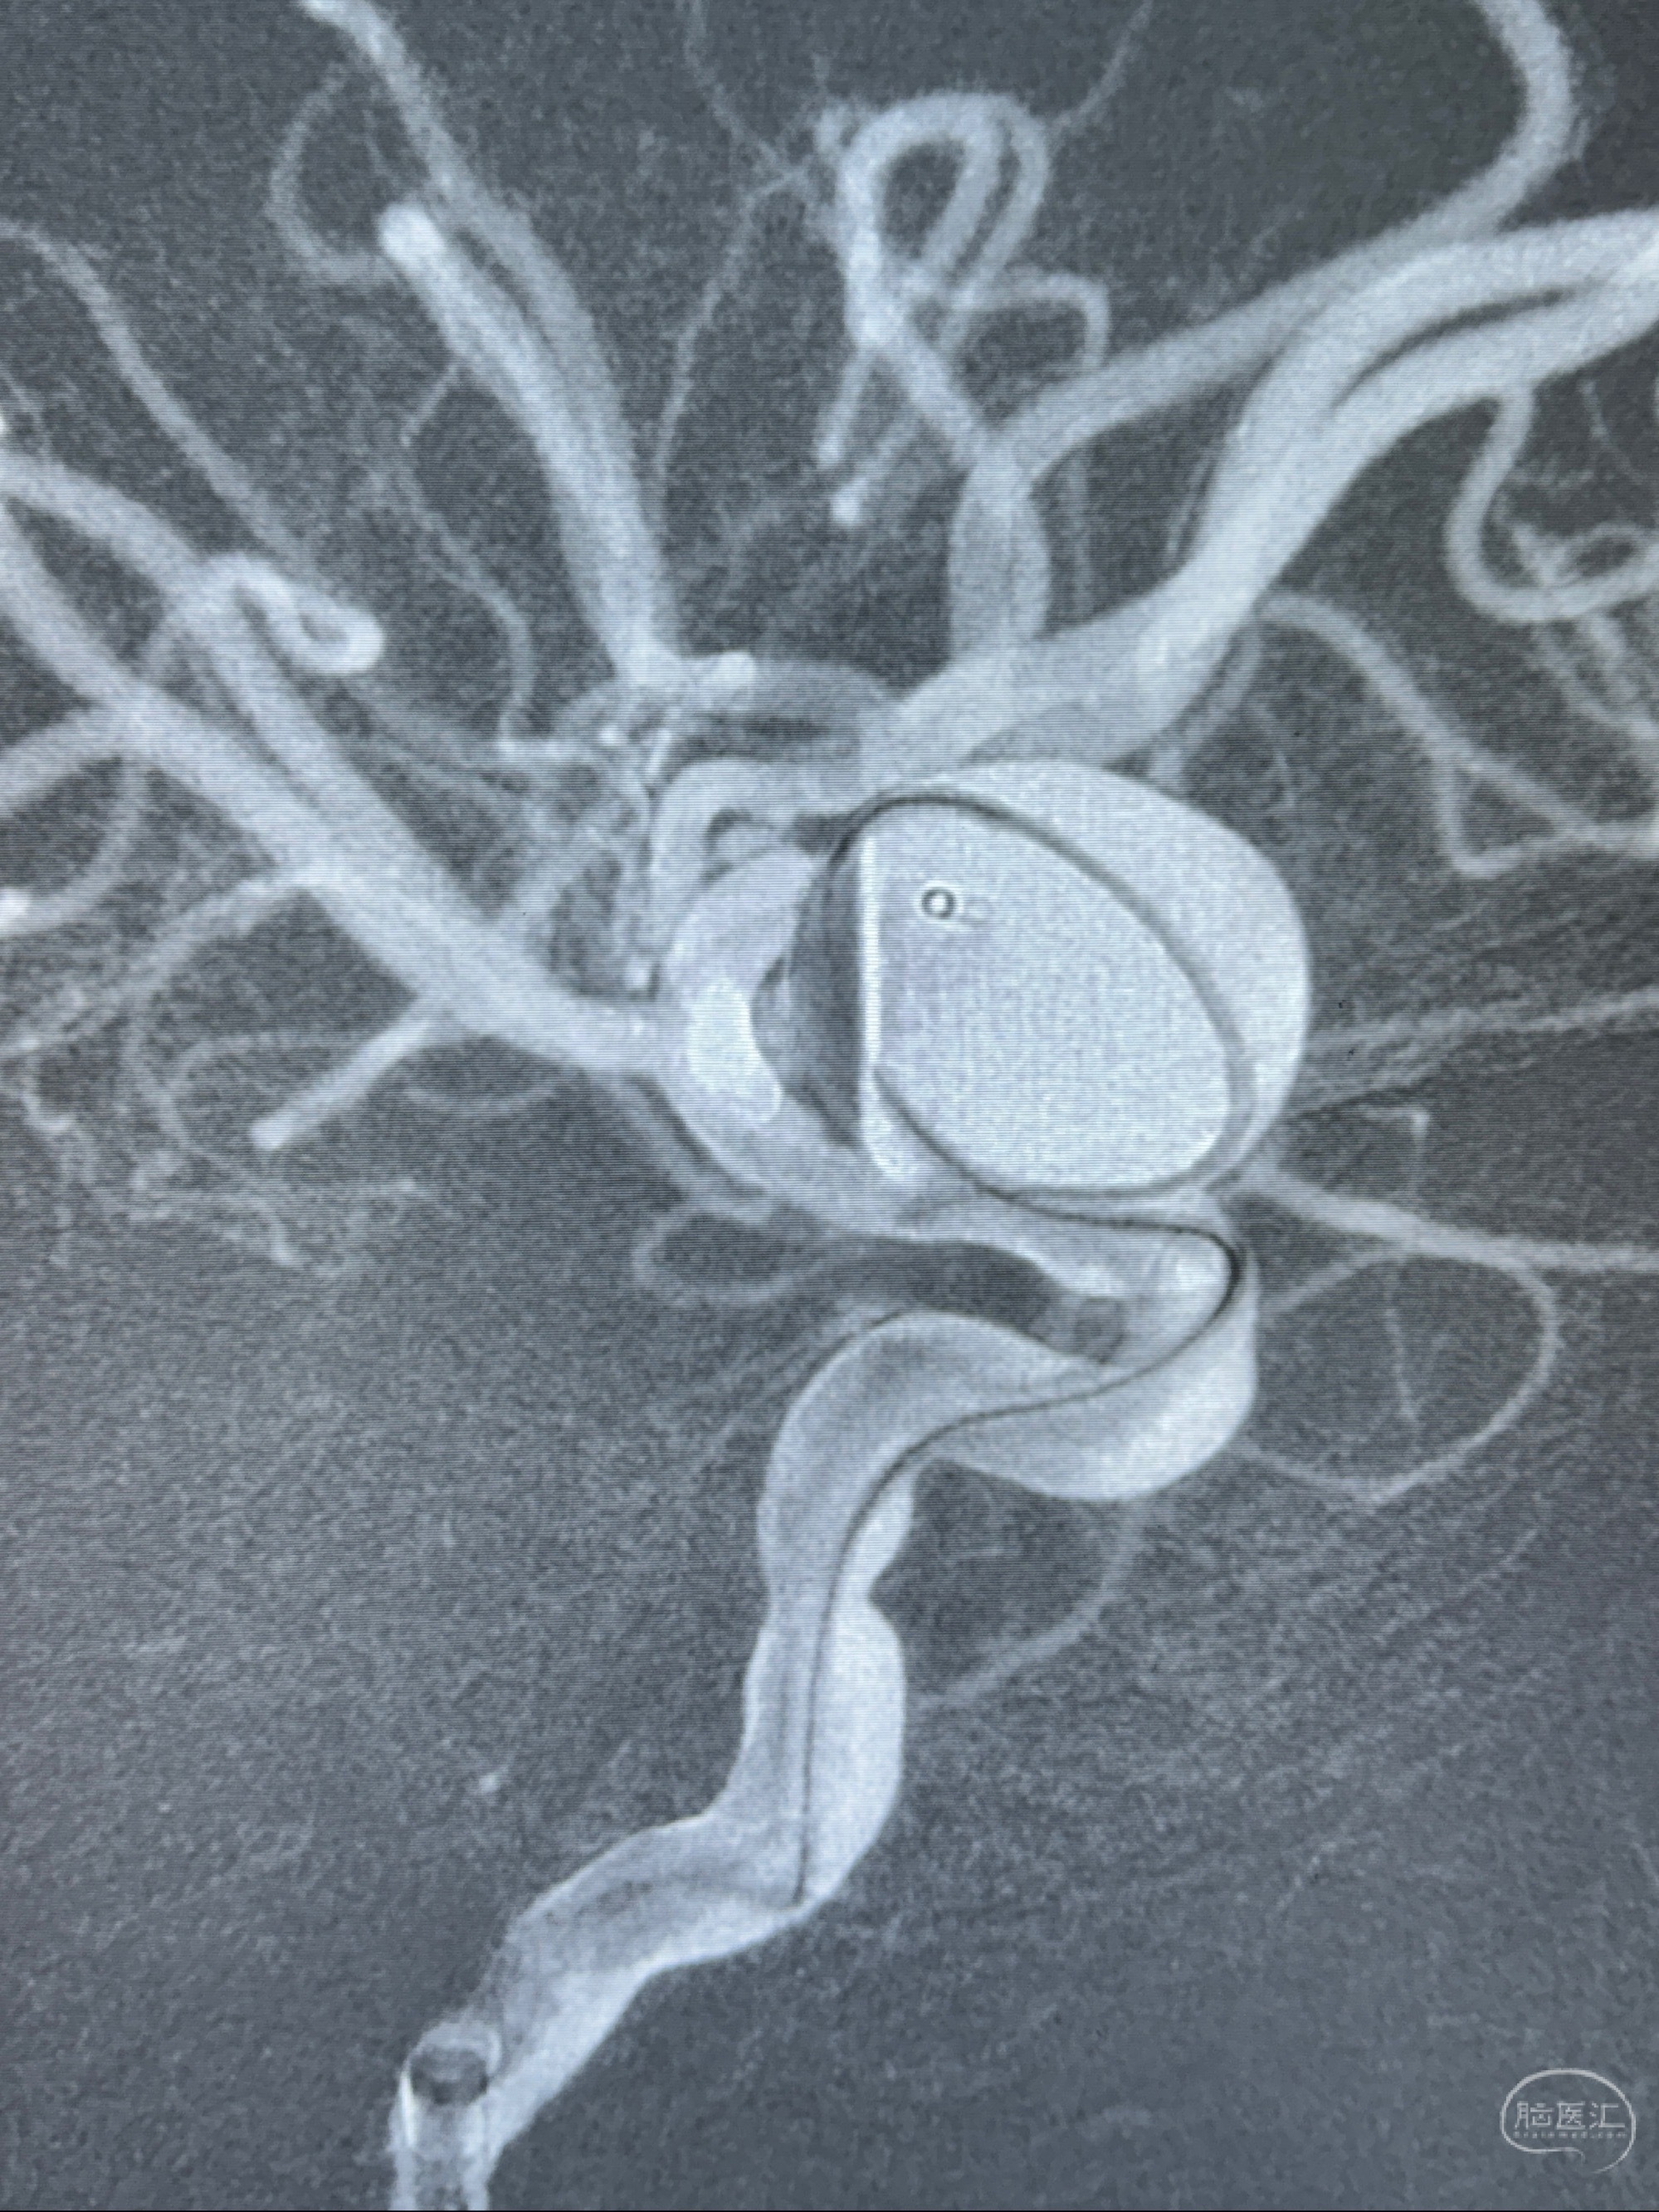

旋转3D展示动脉瘤局部的血管构筑

测量动脉瘤的大小:16*13.8*7.6mm大小,较原先变大,考虑双抗后瘤内血栓溶解可能

观察动脉瘤腔内的血流动力学情况

4.5-30mmTurbridge密网支架,于M1近心端打开

透视下支架释放满意

多角度显示支架打开情况

造影显示支架贴壁情况